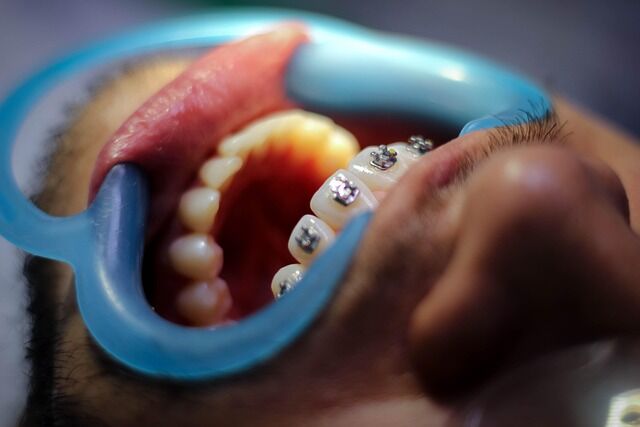

leer mas Los tratamientos de ortodoncia son una opción muy efectiva para mejorar la alineación de los dientes y la apariencia de la sonrisa. Sin embargo, los brackets tradicionales no son un tipo de tratamiento que pase desapercibido. Pero gracias a los avances en tecnologías y materiales aplicados, ahora se pueden usar aparatos ortodónticos que no se